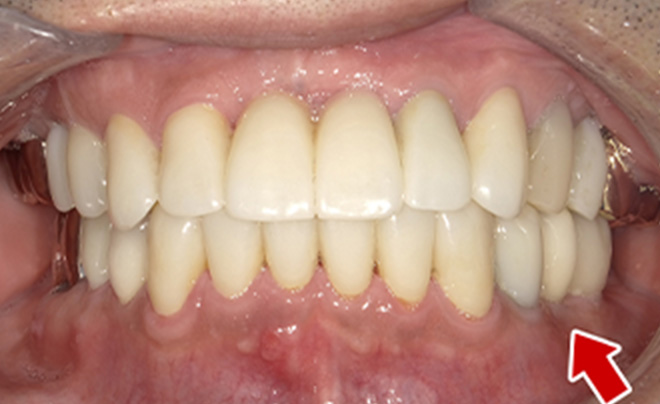

After

| 68歳 男性 | 紹介 |

|---|---|

| 主訴 | れ歯が合わない 食べにくい 人生を豊かにしたい |

| 処置内容 |

上顎4本で12歯(オールオン4)、下顎4本5歯 上下抜歯即時埋入、即時荷重(手術当日にインプラントの上に仮歯装着) |

| 治療費用 | 上顎: 約220万(税込) 下顎: 約180万円(税込) |

| 治療期間 | 上顎: 9ヶ月 下顎: 6ヶ月 |

| リスク |

術後の腫れ、痛み(ピークは3日後、1週間で軽減) 上部構造物、仮歯の破折、人工歯根脱落リスクがあります |